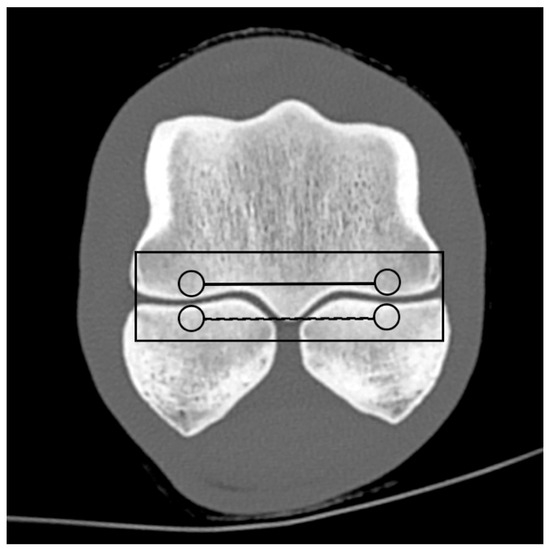

Based on the CT raw data, EAN and ED maps were created from both SSDECT and SBCT images (slice thickness 2 mm), and ROIs were drawn in the virtual monochromatic images (window level 500, window width 2500) using the proprietary software (Raw Data Analysis, CANON Medical and Intellispace Portal 12, Philips Healthcare). Mean EAN/ED values were recorded for each ROI. In total, 29 ROIs and 16 zones were defined for each distal limb. A zone referred to a certain anatomical area, and the mean EAN/ED was calculated from all ROIs included in this area. In the distal aspect of the third metacarpal (MC) and metatarsal (MT) bone, a mid-dorsal image was chosen, and one ROI each was placed in the subchondral bone of the sagittal ridge and the medial and lateral condyle, respectively (dorsal MC/MT zone) (Figure 1). Additionally, a transverse image was chosen at the level of the maximum width of the proximal sesamoid bones (PSB), i.e., at the transition from the distal to the mid-third of the PSBs, and 1 ROI each was placed in the palmar/plantar subchondral bone of the medial and lateral metacarpal/metatarsal condyle (plantar MC/MT zone) and the dorsal subchondral bone of the medial and lateral proximal sesamoid bone (PSB zone) (Figure 2). The mean of all palmar/plantar ROIs in the FJ area (plantar MC/MT and PSB ROIs) represented the palmar/plantar FJ zone (Figure 2). In the first (P1) and second (P2) phalanx, a mid-dorsal image was chosen at the level of the marrow cavity or nutrient foramen, respectively, and in the third phalanx (P3), a dorsal image was chosen parallel to the dorsal surface of the bone at the level of the solar canal. Three ROIs each (medial and lateral fovea, sagittal groove or extensor process) were drawn in the proximal subchondral bone (proximal P1/P2/P3 subchondral zone) and trabecular bone (proximal P1/P2/P3 trabecular zone) distal to the latter in all phalanges (Figure 1 and Figure 3). Larger zones were calculated including all ROIs in the proximal subchondral and trabecular bone of P1, P2 and P3, respectively (proximal epiphyseal P1/P2/P3 zone) (Figure 1 and Figure 3). Moreover, the mean of all dorsal ROIs in the FJ area (distal MC/MT, proximal P1) represented the dorsal FJ zone (Figure 1). A single ROI was also applied to the marrow cavity of P1 (Figure 1). On a mid-dorsal plane of the NB, 3 ROIs were evenly distributed medially, centrally, and laterally within the spongious bone (navicular zone) (Figure 4). All ROIs were of a circular shape with a diameter of 4 mm (smallest ROI possible for both CT units) except for the circular ROI in the marrow cavity of P1, the diameter of which was adapted to the size of the marrow cavity.

Figure 4. Medial, central, and lateral region of interest (ROI; circles) within the spongious bone of a front navicular bone on a mid-dorsal monoenergetic image (detector-based spectral computed tomography, Philips) and navicular zones (mean EAN calculated from all 3 ROIs; continuous line).